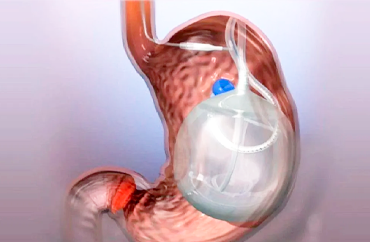

Balón Gástrico

Procedimiento endoscópico No Quirúrgico para la pérdida de peso en personas con obesidad. Consiste en insertar un balón de silicona expandible en el estómago mediante sedación, el cual se llena con una solución salina.